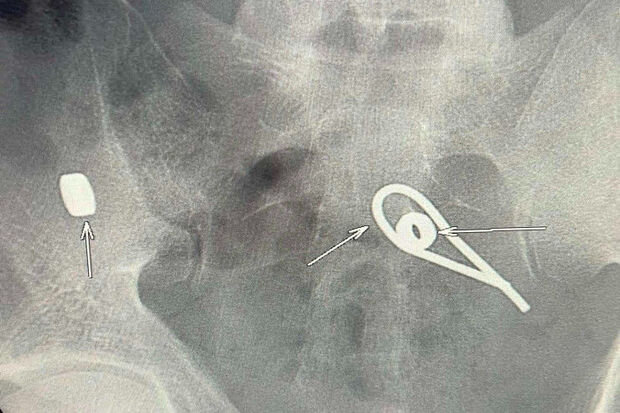

Lent.az xəbər verir ki, bir kişi intihar etmək məqsədilə iki metal qayka və bir ədəd əyilmiş məftil udub.

O dərhal xəstəxanaya yerləşdirilib. Rentgen müayinəsi zamanı kişinin bağırsaqlarında udduğu metal parçalarının yeri müəyyənləşib. Hazırda həkimlər metal əşyaların çıxarılması üçün tədbirlər görürlər.